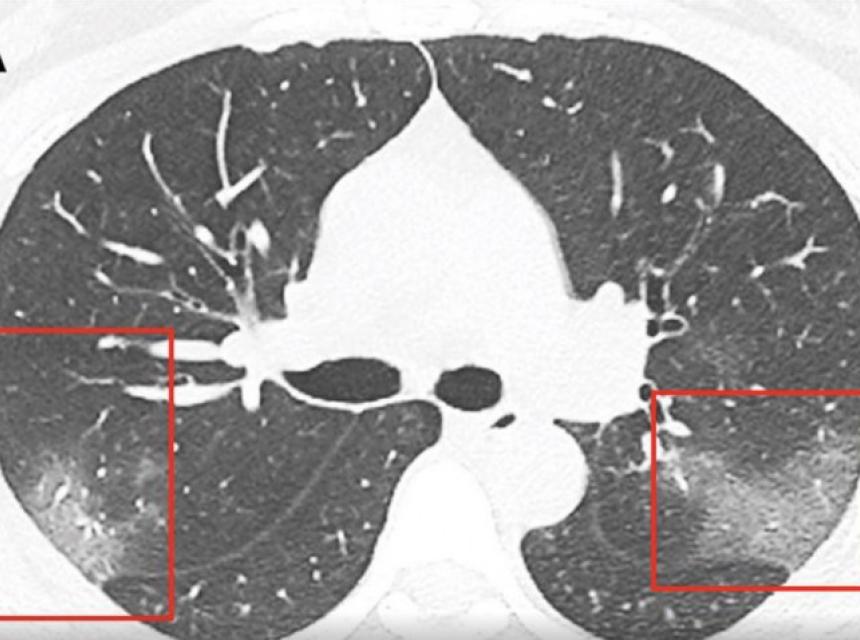

Ljekari su objavili šokantan CT snimak koji najbolje pokazuje šta koronavirus radi plućima.

Na CT snimcima ljekari su uočili bijele sjene, poput takozvanog mliječnog stakla, što ih je upozorilo na to da su pluća djelimično ispunjena tekućinom.

Snimci pluća predstavljeni su u naučnom časopisu "Radiology", a tekst potpisuje grupa ljekara istraživača Prve univerzitetske bolnice u Lanzou.

Navode da kod pacijenata zaraženih koronavirusom dolazi do infekcije koja može oštetiti pluća ili izazvati upalu opasnu po život. Dolazi do oticanja pluća i nagomilavanja tekućine u njima. Pacijenti se zbog toga stavljaju na terapiju lijekovima koji pomažu u otvaranju dišnih kanala.